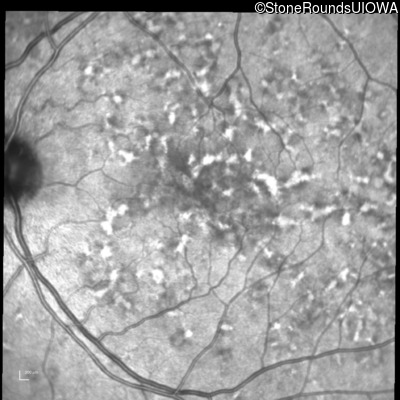

Fluorescein Angiography - Right - 20/40 +2 sc

Exemplar